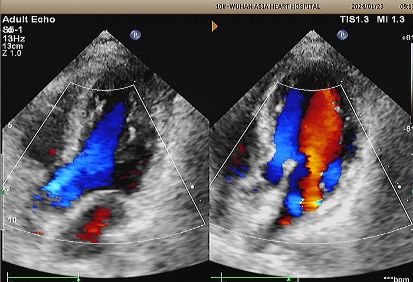

1-jähriges Echo:

No visible disc structures – replaced by 8mm tissue thickening at the septal implant site.

Zero residual shunt (rest or post-Valsalva).

Komplette Absorption des Geräts bestätigt.